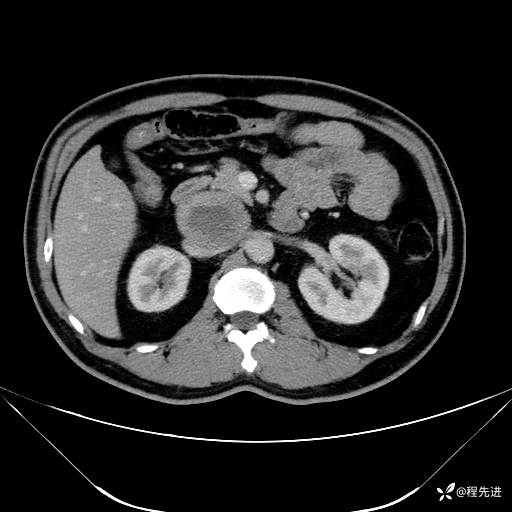

【腹盆】特别精彩病例|发现腹膜后肿物1月余

主诉:发现腹膜后肿物1月余

现病史:患者1月余前查体,行超声检查提示:后腹膜囊实性肿块;慢性胆囊炎伴胆囊内结石;无腹痛腹胀,不伴腹泻发热等;偶感腰背部酸痛。

CT平扫+增强: